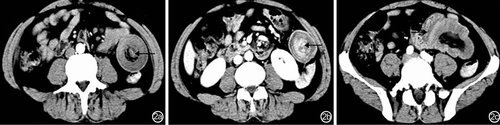

肠梗阻患者CT检查主要表现为回结肠肠壁弥漫性环形增厚,呈水样密度影,不强化或轻度强化;肠外主要表现为肠系膜肿胀、出血,腹腔积液(图7)。

肠系膜上动脉病变患者CT检查主要表现为肠壁广泛均匀中度增厚;肠外主要表现为腹膜炎和腹腔积液(图7)。

肠扭转患者CT检查主要表现为小肠局限性中重度增厚;肠外主要表现为腹膜炎、腹腔积液(图7)。(点击图片可查看原图)

图7 肠扭转并肠系膜血管病变患者CT检查特征 7a:平扫肠梗阻、肠系膜根部扭转(↓),轻度均匀强化,空肠扩张、腹腔积液(→);7b:动脉期回肠壁中度弥漫性均匀增厚(↑),明显均匀强化;7c:静脉期肠系膜上动脉回肠支夹层(↓)、空肠扩张(→)、腹腔积液

急性阑尾炎患者CT检查主要表现为回盲部和回肠末段肠壁局限性环形向心性增厚,呈低密度“双环”、“三环”或“靶征”,明显强化;肠外主要表现为腹膜炎、腹腔脓肿、阑尾增粗(图8)。(点击图片可查看原图)

图8 急性阑尾炎患者CT检查特征 8a:平扫回盲部及回肠末端肠壁增厚,呈“环靶征”,空肠扩张、积液(→);8b:动脉期内外肠壁明显强化(→),中间水肿不强化;8c:静脉期回盲部左侧局限性腹腔积液(←)